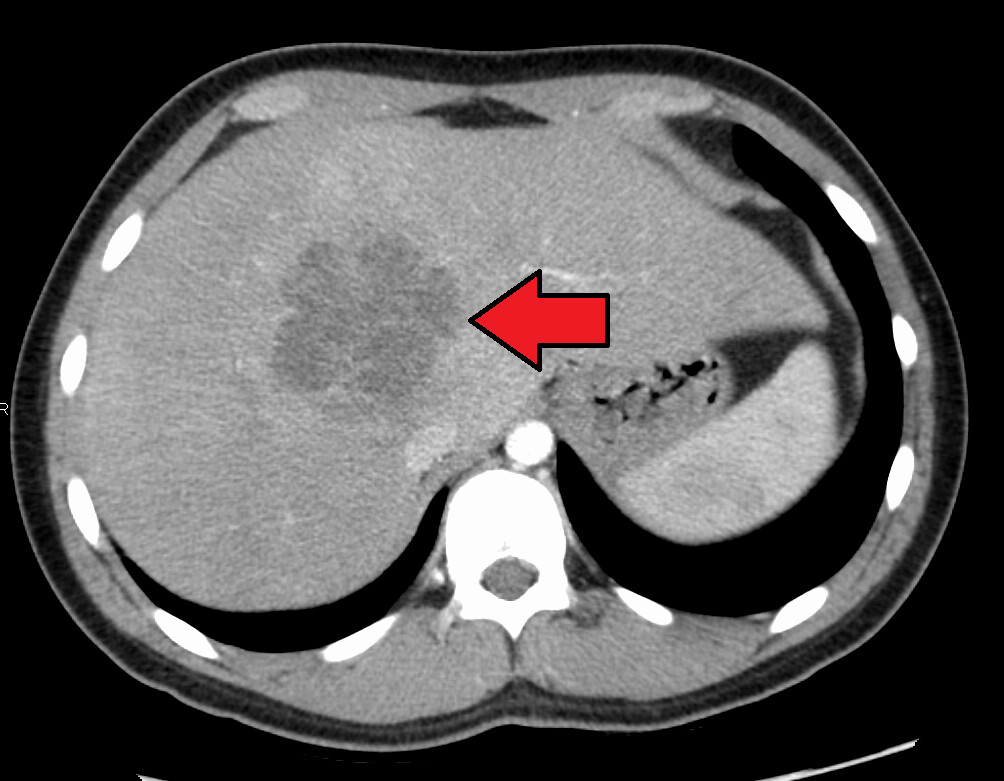

Абсцесс печени кт

Абсцесс печени кт 109 фото